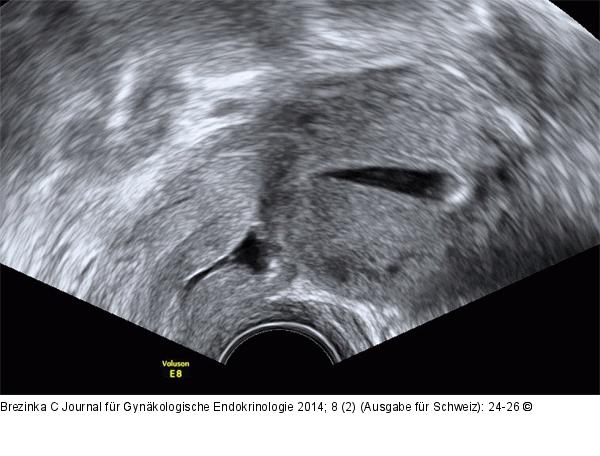

Abbildung 8: Gyn-Ultraschall Darstellung der Sectionarbe bei Kontrastmitteldarstellung mit NaCl (HSU-Hysterokontrastsonographie [HSU). |

Darstellung der Sectionarbe bei Kontrastmitteldarstellung mit NaCl (HSU-Hysterokontrastsonographie [HSU). |